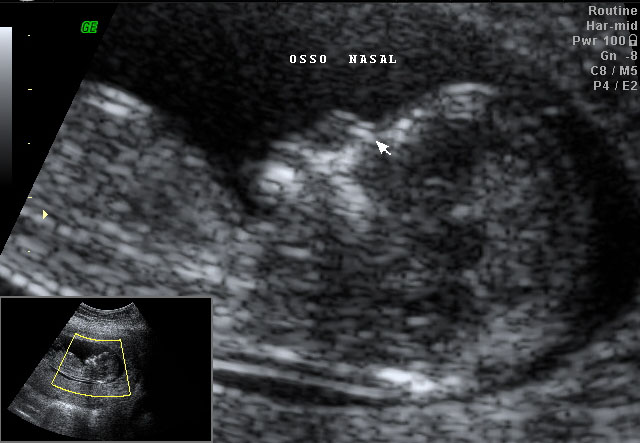

Este exame tem como objetivo avaliação precoce de algumas alterações anatômicas fetais e rastreamento das cromossomopatias mais comuns, como trissomia 21 (síndrome de Down), trissomia do 18 (síndrome de Edwards) e trissomia do 13 (síndrome de Patau), através da análise de alguns marcadores como translucência nucal, osso nasal e ducto venoso.

É realizado quando o feto tem entre 45 e 84 mm de comprimento cabeça-nádega, o que geralmente corresponde a 11 e 14 semanas, respectivamente, podendo ser

realizada por via abdominal ou via vaginal, a depender da via que

oferecer melhor qualidade de imagem.